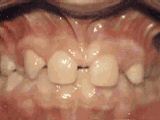

missing lateral incisors

This patient's lateral incisors were congenitally missing. She had braces for twenty months to move the teeth into the correct position, then the missing teeth were replaced with bonded "Maryland" bridges.